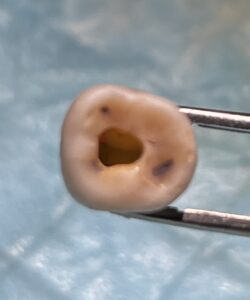

T先生

このセミナーに来て、たまたま大学の同級生のI先生と再会したT先生のテストケースは以下だ。

MB2を探索しようとしてファイルが破折したのでやり直してテストケースを3つも行ったT先生。

いやあ上手いです。

先生も保険でなく、自費で根管治療を行うべき人ですよ。